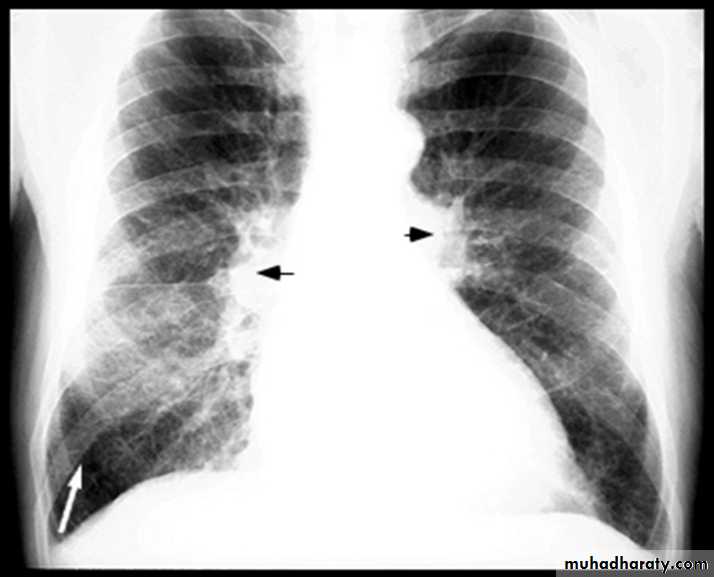

BNP brain natriuretic pepetideChest X-ray in Heart Failure

CardiomegalyCephalization of the pulmonary vessels

Kerley B-lines

Pleural effusions

Cardiomegaly Pulmonary vessel congestion

Pulmonary Edema due to Heart Failure

Kerley B lines